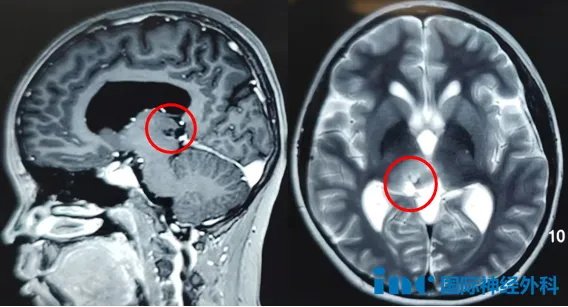

影像

在這場手術(shù)之前,這個膠質(zhì)瘤已經(jīng)在新城小小的身體中蟄伏了6年之久。2019年,新城總是抱怨自己脖子不舒服、低頭困難,在當?shù)蒯t(yī)院檢查后僅查出了輕微的嵴柱側(cè)彎。然而,不久之后,新城開始出現(xiàn)視力模煳,這讓父母察覺到不安,于是他們決定帶孩子前往醫(yī)院檢查。等看到檢查結(jié)果,父母這才驚覺,原來孩子的腦袋中長了一個腫瘤!

父母下定決心鏟除孩子成長路上的障礙,然而醫(yī)生的一番話卻如一盆涼水兜頭而下:“腫瘤已經(jīng)引發(fā)梗阻性腦積水,可以先進行三腦室底造瘺術(shù)來緩解,但由于腫瘤長在右側(cè)丘腦-中腦,手術(shù)風險太大,不能進行腫瘤切除手術(shù)。”

根據(jù)巴教授術(shù)前的評估,新城的腫瘤切除難度較高,不僅由于腫瘤位置在腦干中腦-丘腦這一核心區(qū)域,真正的牽一發(fā)而動全身,更在于腫瘤邊界不清。正常腦組織與腫瘤之間沒有一條清晰的分界線,而是一個漸變的、浸潤的區(qū)域,這導致手術(shù)難度極大,對術(shù)者的操作精度要求極高。